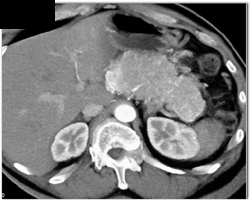

Carcinoma of the Pancreas